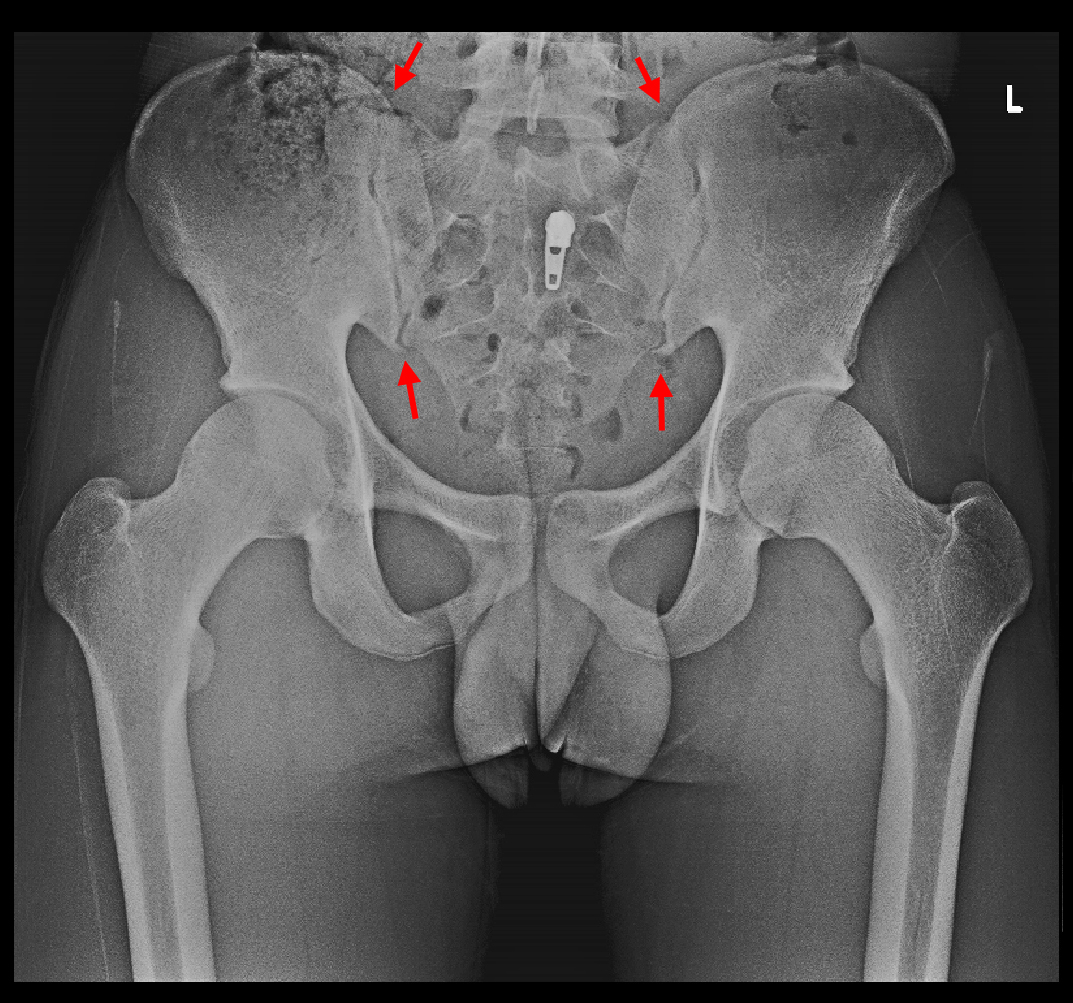

16才男図5.jpg

16才男図6.jpg

リハビリテーションの目的はレントゲン像の赤矢印の仙腸関節(脊椎の再下端部の仙骨と両側腸骨の関節)の動きを拡大誘導して、股関節の深い屈曲で大腿骨頭が関節唇を損傷する動きを緩和してやろうという対応となります。